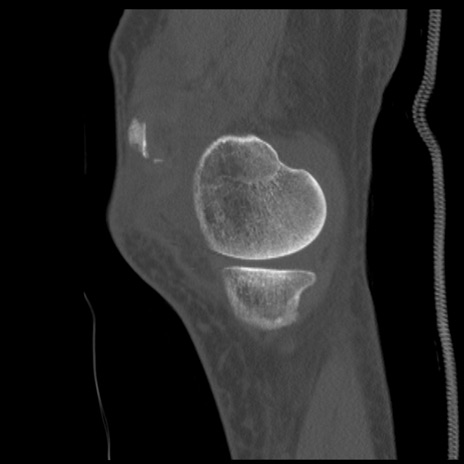

症例28 右膝関節CT(矢状断像)

右膝関節CT

横断像